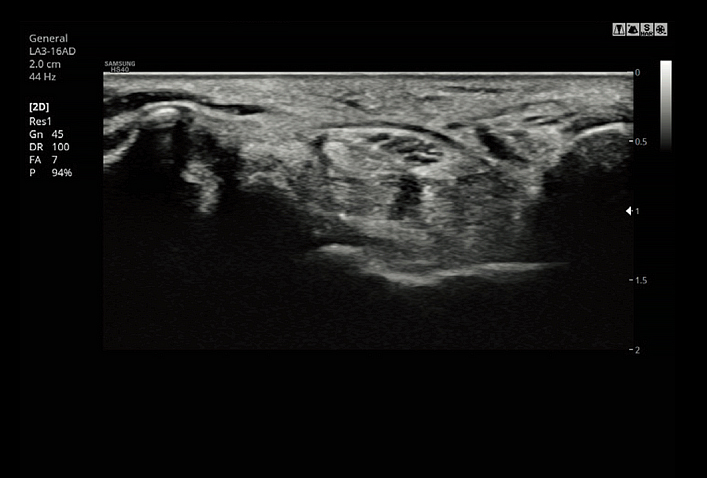

HQ-Vision™ provides clearer images by mitigating the characteristics of ultrasound images that are slightly blurred than the actual vision.

S-Harmonic™ reduces signal noise and provides more uniform ultrasound images by improving near to far image clarity.

ClearVision provides clearer tissue boundaries using the noise reduction filter and generates sharp 2D images. It reduces halo artifact that occurs when the tissue contour is enhanced, and removes noises on the tissue boundaries.